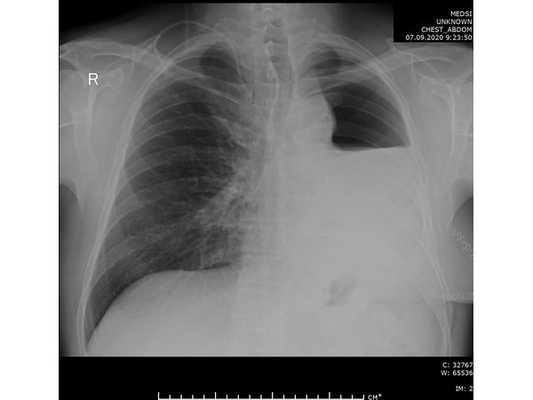

- Рентгенография органов грудной клетки. Этот метод в большинстве случаев не позволяет непосредственно визуализировать опухоль в легких, тем не менее по косвенным признакам можно заподозрить ее наличие.

При дальнейшем дообследовании, по данным рентгенографии и компьютерной томографии органов грудной клетки выявлено новообразование в нижней доле левого лёгкого. После этого пациент был направлен на консультацию к торакальному онкологу.

Проведена профилактическая стандартная антибактериальная терапия в течение пяти суток. По данным контрольной рентгенографии, отмечено смещение средостения в оперированную сторону.